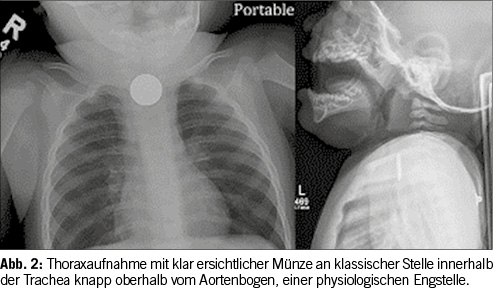

Jedoch gibt es auch hierbei einige Einschränkungen. Schlecht erkennbare Gegenstände, wie zum Beispiel kleine Fischgräten oder Hühnerknochen, sind im Körper häufig zusätzlich durch dichte Organe, oder Knochen verdeckt und bleiben somit dem Auge vorenthalten.[7] Es kommt vor, dass ein Gegenstand auf dem Referenzbild gut erkennbar ist, beim Patienten auf den Röntgenaufnahmen jedoch nicht. Es gibt neben den klinischen Symptomen wie zum Beispiel starke Speichelbildung, Übelkeit, Schluckbeschwerden oder Atemnot sowohl direkte als auch indirekte Befunde im Röntgenbild, welche auf einen Fremdkörper hinweisen. Direkte Hinweise sind auf Röntgenbildern einfach ersichtliche, röntgendichte Objekte, wie zum Beispiel Münzen oder Batterien (Abbildung 2). Falls der Fremdkörper nicht röntgendicht ist, können indirekte Befunde wie zum Beispiel eine fokale Obstruktion einer Darmschlinge, eine Verlagerung vom Mediastinum oder die fehlende ‘Luftsäule’ in einem Bronchus auf einen nicht röntgendichten Fremdkörper hinweisen.